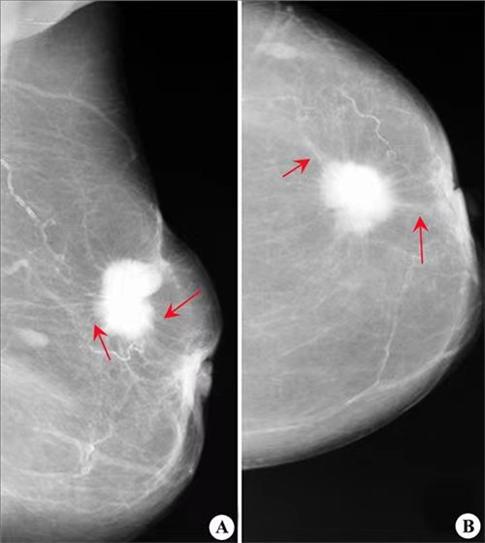

钼靶优势

钼靶对微钙化(砂砾样、点簇状)非常敏感,因此对乳腺肿块良恶性的鉴别更有优越性,尤其对还没有形成结节的早期乳腺癌的诊断非常有价值。

2、对于乳房小的的患者,肿块靠近胸壁,病灶无法显像,容易出现漏诊;

50岁(绝经后)女性,腺体逐渐萎缩,转变成多脂肪少腺体型的乳房,那么做钼靶检查是非常适合的。